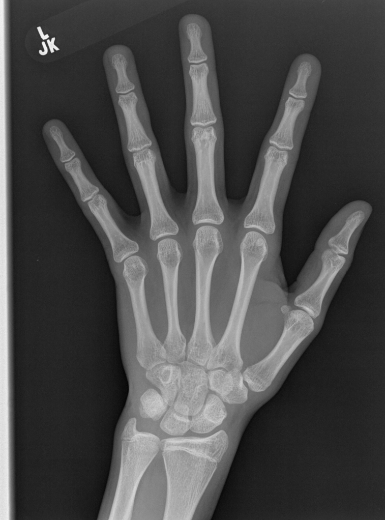

Deep neural networks are increasingly being used for the analysis of medical images. However, most works neglect the uncertainty in the model's prediction. We propose an uncertainty-aware deep kernel learning model which permits the estimation of the uncertainty in the prediction by a pipeline of a Convolutional Neural Network and a sparse Gaussian Process. Furthermore, we adapt different pre-training methods to investigate their impacts on the proposed model. We apply our approach to Bone Age Prediction and Lesion Localization. In most cases, the proposed model shows better performance compared to common architectures. More importantly, our model expresses systematically higher confidence in more accurate predictions and less confidence in less accurate ones. Our model can also be used to detect challenging and controversial test samples. Compared to related methods such as Monte-Carlo Dropout, our approach derives the uncertainty information in a purely analytical fashion and is thus computationally more efficient.